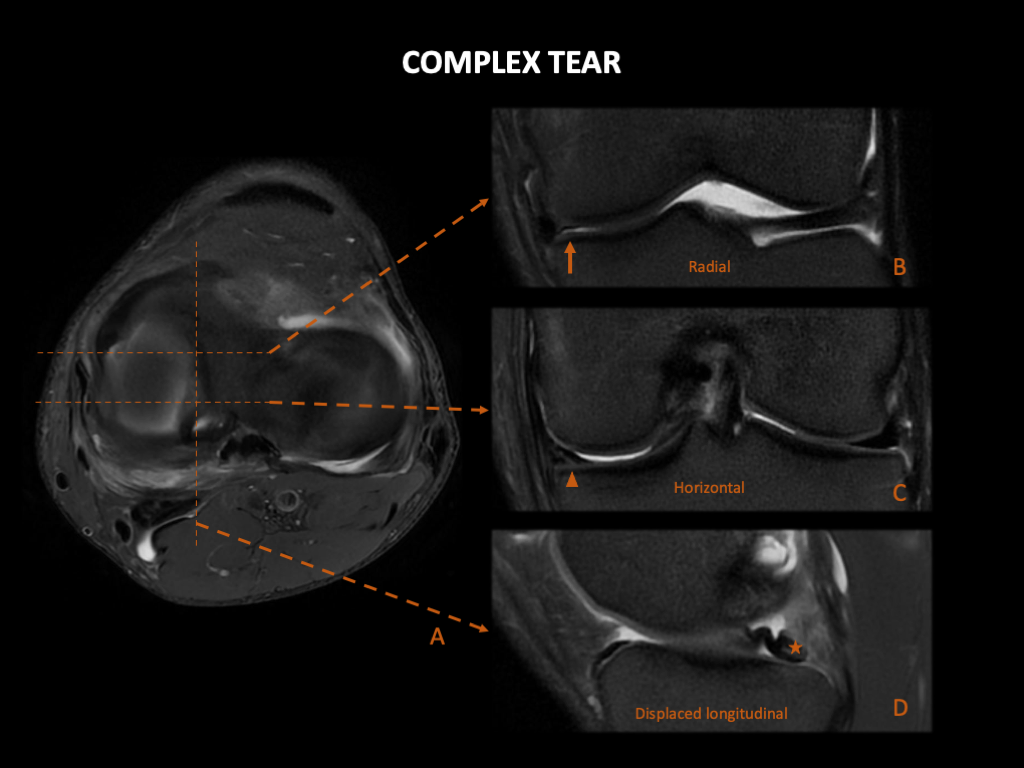

复杂撕裂:在某些情况下,上述撕裂类型中的一个或多个可能同时出现在同一患者身上。

图 11:男,38岁,复杂撕裂,膝关节疼痛,查体结果呈内侧半月板损伤。左膝 3T MRI:(A) Ax PD FS、(B) 和 (C) Cor T2WIFS 和 (D) Sag PD FS 显示复杂的撕裂,始于内侧半月板前部的放射状撕裂(箭) ,延续为水平撕裂(箭头),并以垂直撕裂结束,其中碎片(星形)移向髁间切迹,类似于“桶状”。